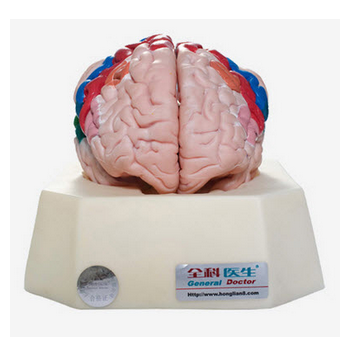

大腦皮質(zhì)功能定位模型 GD/A18205簡介:模型置于基板上,可分解成2部分,包括大腦半球、小腦和腦干等。著色顯示大腦皮質(zhì)功能定位區(qū)域。共顯示10個部位■ 尺寸:自然尺寸■ 材質(zhì):進口PVC材料、進口...